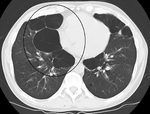

قد يفيد تصوير الصدر بالأشعة السينية والعد الدموي الشامل في استبعاد أسباب أخرى في وقت التشخيص.[52] والسمات المميزة للأشعة السينية هي التمدد الشديد للرئتين، وانبساط الحجاب الحاجز، وزيادة حيز الهواء خلف القص، والأمراض الجلدية، في حين أنها قد تساعد في استبعاد أمراض الرئة الأخرى مثل ذات الرئة ووذمة الرئة أو الاسترواح الصدري.[53] يمكن لصورة الصدر عالية الوضوح باستخدام التصوير المقطعي المحوسب بالأشعة السينية أن تبين توزيع النفاخ الرئوي في جميع أنحاء الرئتين ويمكن أيضاً أن تكون مفيدة في استبعاد أمراض الرئة الأخرى.[11] إذا لم يكن مخططاً لإجراء عملية جراحية، فهذا نادراً ما يؤثر على العلاج.[11] ويتم استخدام غازات الدم الشرياني لتحديد مدى الحاجة إلى الأكسجين؛ ويوصى به لمن يُتوقع أن يكون حجم الزفير القسري لديهم1 أقل من 35%، والذين لديهم تشبع أكسجين محيطي أقل من 92% والذين تظهر لديهم أعراض قصور القلب الاحتقاني.[10] في مناطق العالم التي يشيع فيها نقص مضاد التريبسين ألفا-1، يجب أن يوضع في الاعتبار اختبار الأشخاص المصابين بمرض الانسداد الرئوي المزمن (خاصة من هم دون سن 45 ولديهم نفاخ رئوي يؤثر على الأجزاء السفلية من الرئتين).[10]